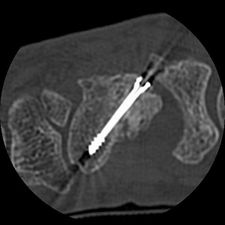

Die ESWT kann im Rahmen der konservativen Bruchbehandlung (z.B. Gips), in Kombination mit einer Operation (Stabilisierung von Brüchen, Auffüllen von Knochendefekten, etc.) oder zu einem späteren Zeitpunkt nach einer Operation erfolgen. Einliegendes Metall beeinträchtigt nicht die Anwendung.